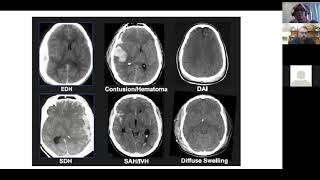

Imaging in Brain Trauma: Principals, Nuances and Future Directions by Mr Regunath Kandasamy